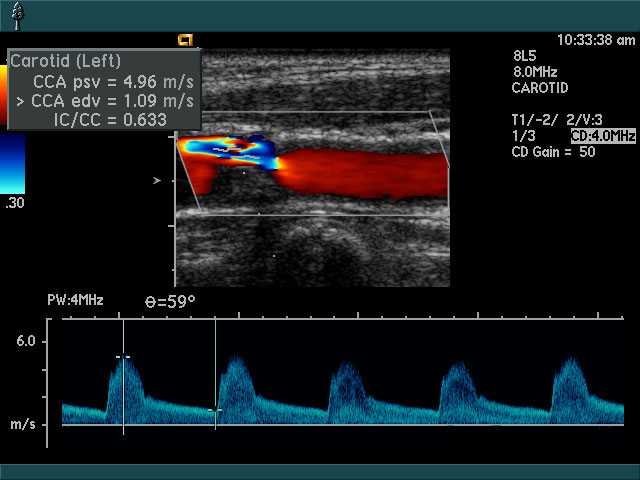

• Halsschlagadern